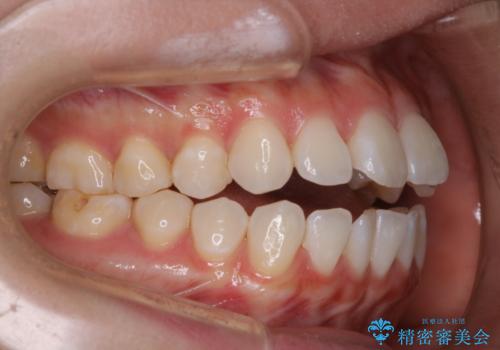

前歯で噛めない:オープンバイト(開咬)を非抜歯インビザラインで治療

オープンバイトの方への治療は、通常抜歯を行いワイヤーによる矯正治療を行うことが多いですが、今回はインビザラインの特性を生かし、非抜歯にて綺麗な歯並びを作ることが出来ました。

舌癖がある方は、歯を内側から押し出す力が日常的に働くため、矯正治療後も歯と歯の隙間が開いてしまうなどの後戻りのリスクが高いことが知られています。舌の正しいポジショニングやお口周りの筋肉のトレーニングを行うことで後戻りのリスクを減らすことが可能です。